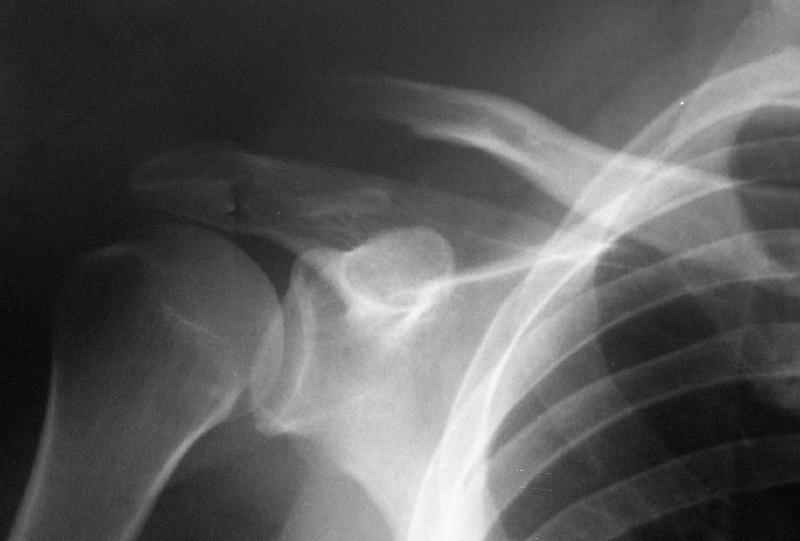

АПК> молодому пациенту по поводу оскольчатого перелома акромиального конца

АПК> ключицы

Что за редкая травма? Никогда такой не видел... Покажите?

Судя по представленному снимку - существует дистальный фрагмент, который замечательно, вроде бы, связан с акромионом... Что мешает "пришпилить" проксимальный к дистальному и закрепить его при помощи спиц? или как-то по иному (аппарат?)... В любом случае зачем пока идти большим разрезом на ключично-клювовидную связку? почему не пойти от меньшего?

"Толкатель" - укороченная спица с упором. На первичных снимках - оскольчатый перелом, отдельный фрагмент с местом прикрепления кл-кл связки сместился каудально.

Первично правильно сопоставленный перелом (небольшой разрез, спицы) привел бы к тому, что костный фрагмент, отрванный ключично-клювовидной связкой, лег аккурат под своим ложем и тесно к нему... то бишь в итоге сросся бы без проблем... (кстати на вашем снимке костный фрагмент "оскольчатого перелома" консолидирован... то есть даже достигнутая вами несостоятельная фиксация привела к приростанию авульзионно оторванного

фрагмента)

АПК> На первичных снимках -

АПК> оскольчатый перелом, отдельный фрагмент с местом прикрепления кл-кл

АПК> связки сместился каудально.

Я бы назвал данный перелом как перелом с костной авульзией ключично-клювовидной связи... Потому как данный фрагмент лежит вне основной зоны перелома...